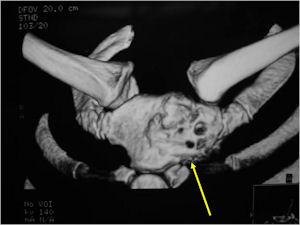

CT Scan:

- More useful for detecting mineralization and evaluating extent of bone destruction than plain X-ray

MRI:

- Also useful in determining extent

- There is often extensive edema around the tumor in the surrounding bone and soft tissues that can lead to a misdiagnosis of a malignant tumor.